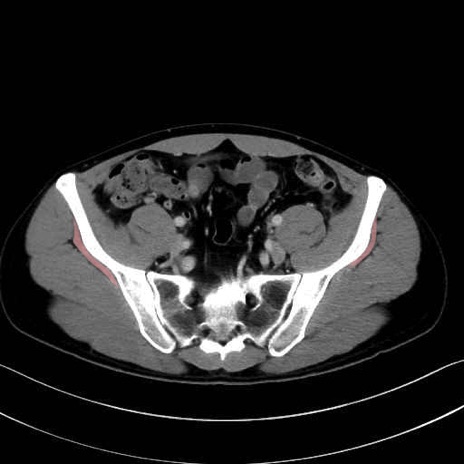

小殿筋 (Gluteus minimus)